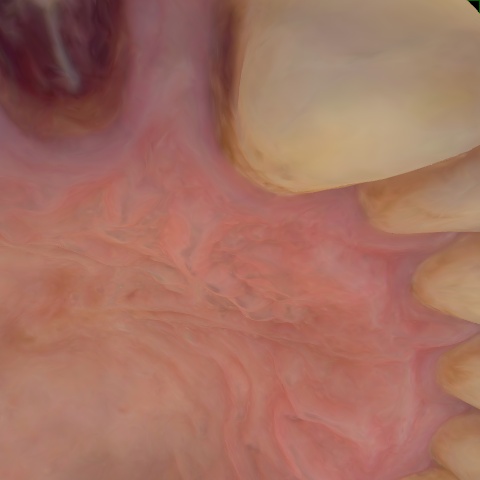

Annotated as "Good"

Original Image Rendering Image